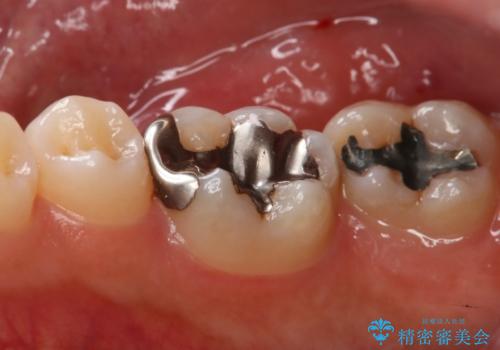

- 右上下6番の銀歯のやり変えを希望された患者様です。

切削量・形態を考慮し、上はセラミッククラウン、下はセラミックインレーでの治療を選択しました。

上はう蝕が歯頚部まで達していたのでクラウンでの治療を選択しました。

銀歯直下もう蝕が進行していたので全て除去した上でCRにて裏層しています。

下はクラウンほど切削量が多くないと判断し、インレーでの治療を選択しました。